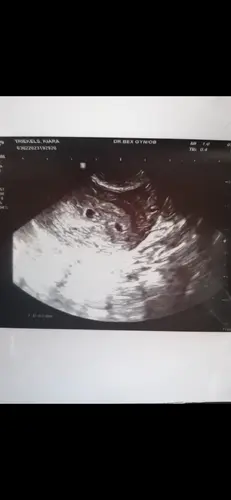

Afgelopen maandag was ik 6 weken zwanger en heb ik de 1e echo gehad. De verloskundige zag al heel snel 1 mooi kloppend hartje.馃グ

Toen ze even verder keek dacht ze er nog 1 te zien. Aangezien ze het niet duidelijk in beeld kreeg, vroeg ze of ze inwendig mocht kijken.

Inwendig werd het beeld niet duidelijker.

Zojuist de echo gehad.

1 kindje te zien met een mooi kloppend hartje geschat op 7+5 dagen. 馃グ

2e wel een vruchtzak te zien, maar verder niks. Dus waarschijnlijk heel vroeg mis gegaan of nooit gegroeid.